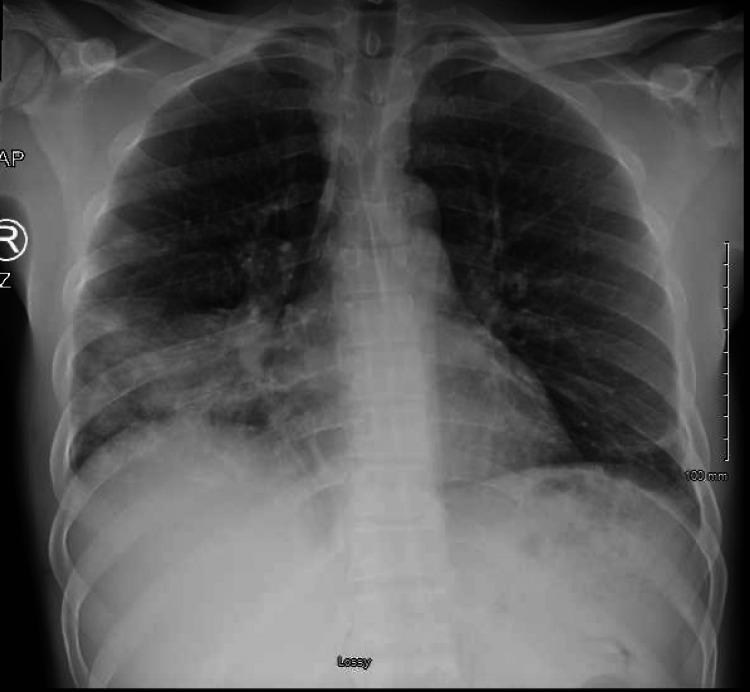

We report a case of a 41-year-old male diagnosed with pulmonary coccidioidomycosis and pulmonary embolism (PE) based on a point-of-care ultrasound (POCUS) finding who was suspected to be malingering for right-sided chest pain considering his psychiatric history. POCUS was performed and showed right ventricular strain with a D-shaped left ventricle and B-lines with subpleural consolidations, and PE was confirmed with computed tomography pulmonary angiography. No other risk factors for PE were found except for coccidioidomycosis. The patient was treated with apixaban and fluconazole and discharged in stable condition. We discuss the usefulness of POCUS in diagnosing PE and the very rare association between coccidioidomycosis and PE.

我们报告了一例41岁男性病例,该患者基于床旁超声(POCUS)检查结果被诊断为肺球孢子菌病和肺栓塞(PE)。考虑到他的精神病史,曾怀疑他右侧胸痛是装病。进行了POCUS检查,结果显示右心室劳损,左心室呈D形,并有胸膜下实变的B线征,随后通过计算机断层扫描肺血管造影证实了肺栓塞。除球孢子菌病外,未发现其他肺栓塞危险因素。该患者接受了阿哌沙班和氟康唑治疗,出院时病情稳定。我们讨论了POCUS在诊断PE中的作用以及球孢子菌病与PE之间极为罕见的关联。